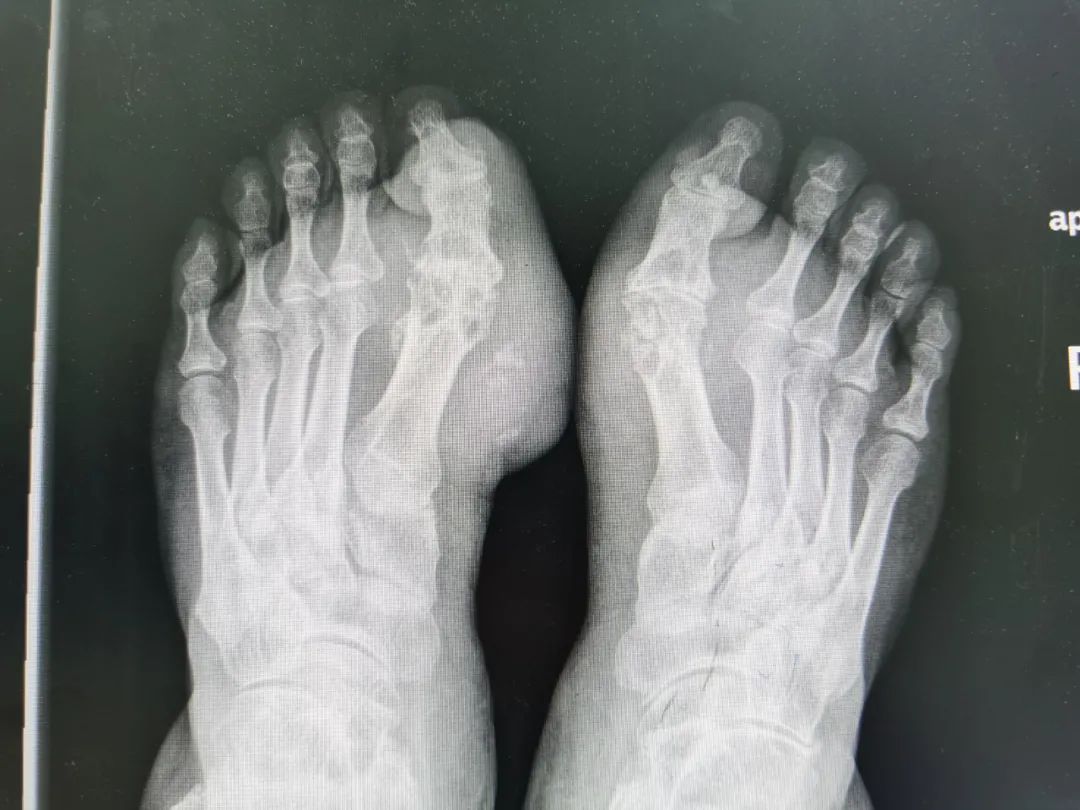

從2012年開始,李先生雙腳變形了,大腳趾的關(guān)節(jié)周圍慢慢鼓起來,似乎里面有什么東西在不斷增生,形成雞蛋大的鼓包,又紅又腫,而且疼痛難忍,還伴隨發(fā)麻。如今,年過五旬的他雙腳已經(jīng)不能正常踩地了,走路變成了痛苦的折磨。

雙腳長出雞蛋大的痛風(fēng)石  醫(yī)生做手術(shù)取出

3月21日,李先生在家人的陪伴下來到寧夏回族自治區(qū)人民醫(yī)院西夏分院就診。骨科副主任醫(yī)師宋強(qiáng)接診后,發(fā)現(xiàn)患者腳趾關(guān)節(jié)處的皮膚被撐得特別薄,幾乎透明,肉眼就能看見皮膚里面的白色物質(zhì),馬上就要把皮膚撐破了。

宋強(qiáng)為他安排了尿酸檢測,結(jié)果顯示患者的‌‌尿酸值達(dá)到 500多單位,而健康男性的尿酸值應(yīng)該在420‌‌以下,初步判斷為痛風(fēng)性關(guān)節(jié)炎。除此之外還查了雙腳的雙源CT,發(fā)現(xiàn)雙腳大拇趾的關(guān)節(jié)處有大量綠色‌物質(zhì)析出,醫(yī)生稱之為:痛風(fēng)石,正是這些石頭在刺激腳趾,讓患者疼痛。